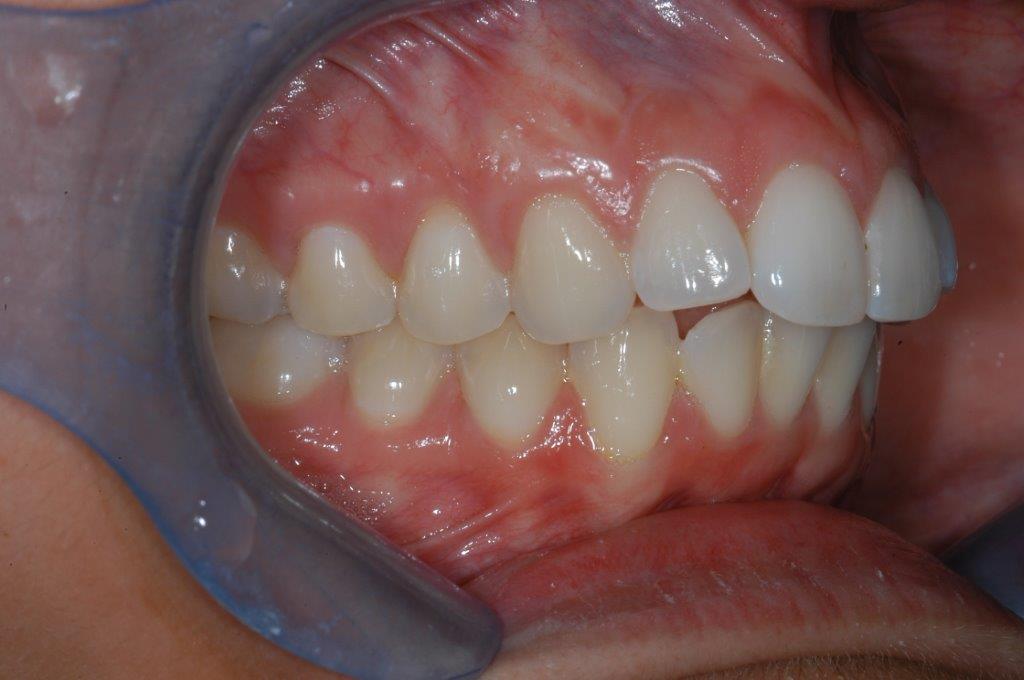

This young patient was self-conscious about the appearance of her short teeth and gummy smile. Through crown lengthening and tooth whitening procedures, we were able to create a beautiful, more mature smile.